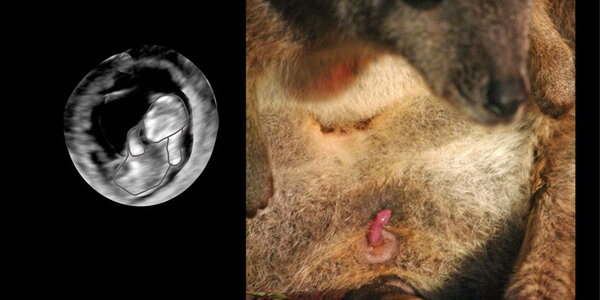

Marsupials represent approximately 6% of all mammal species and include iconic pouched mammals like the kangaroo, wombat and koala. Compared to eutherian mammals like the dog, cow and human, marsupials have ultra-short pregnancies and give birth to very immature, almost embryonic, young that complete most of their development attached to the teat, usually within a pouch.Even kangaroos, the largest extant marsupials, give birth to a newborn that weighs less than one gram and must climb blind and unaided from the birth canal to the pouch.  Using high-resolution ultrasound, …